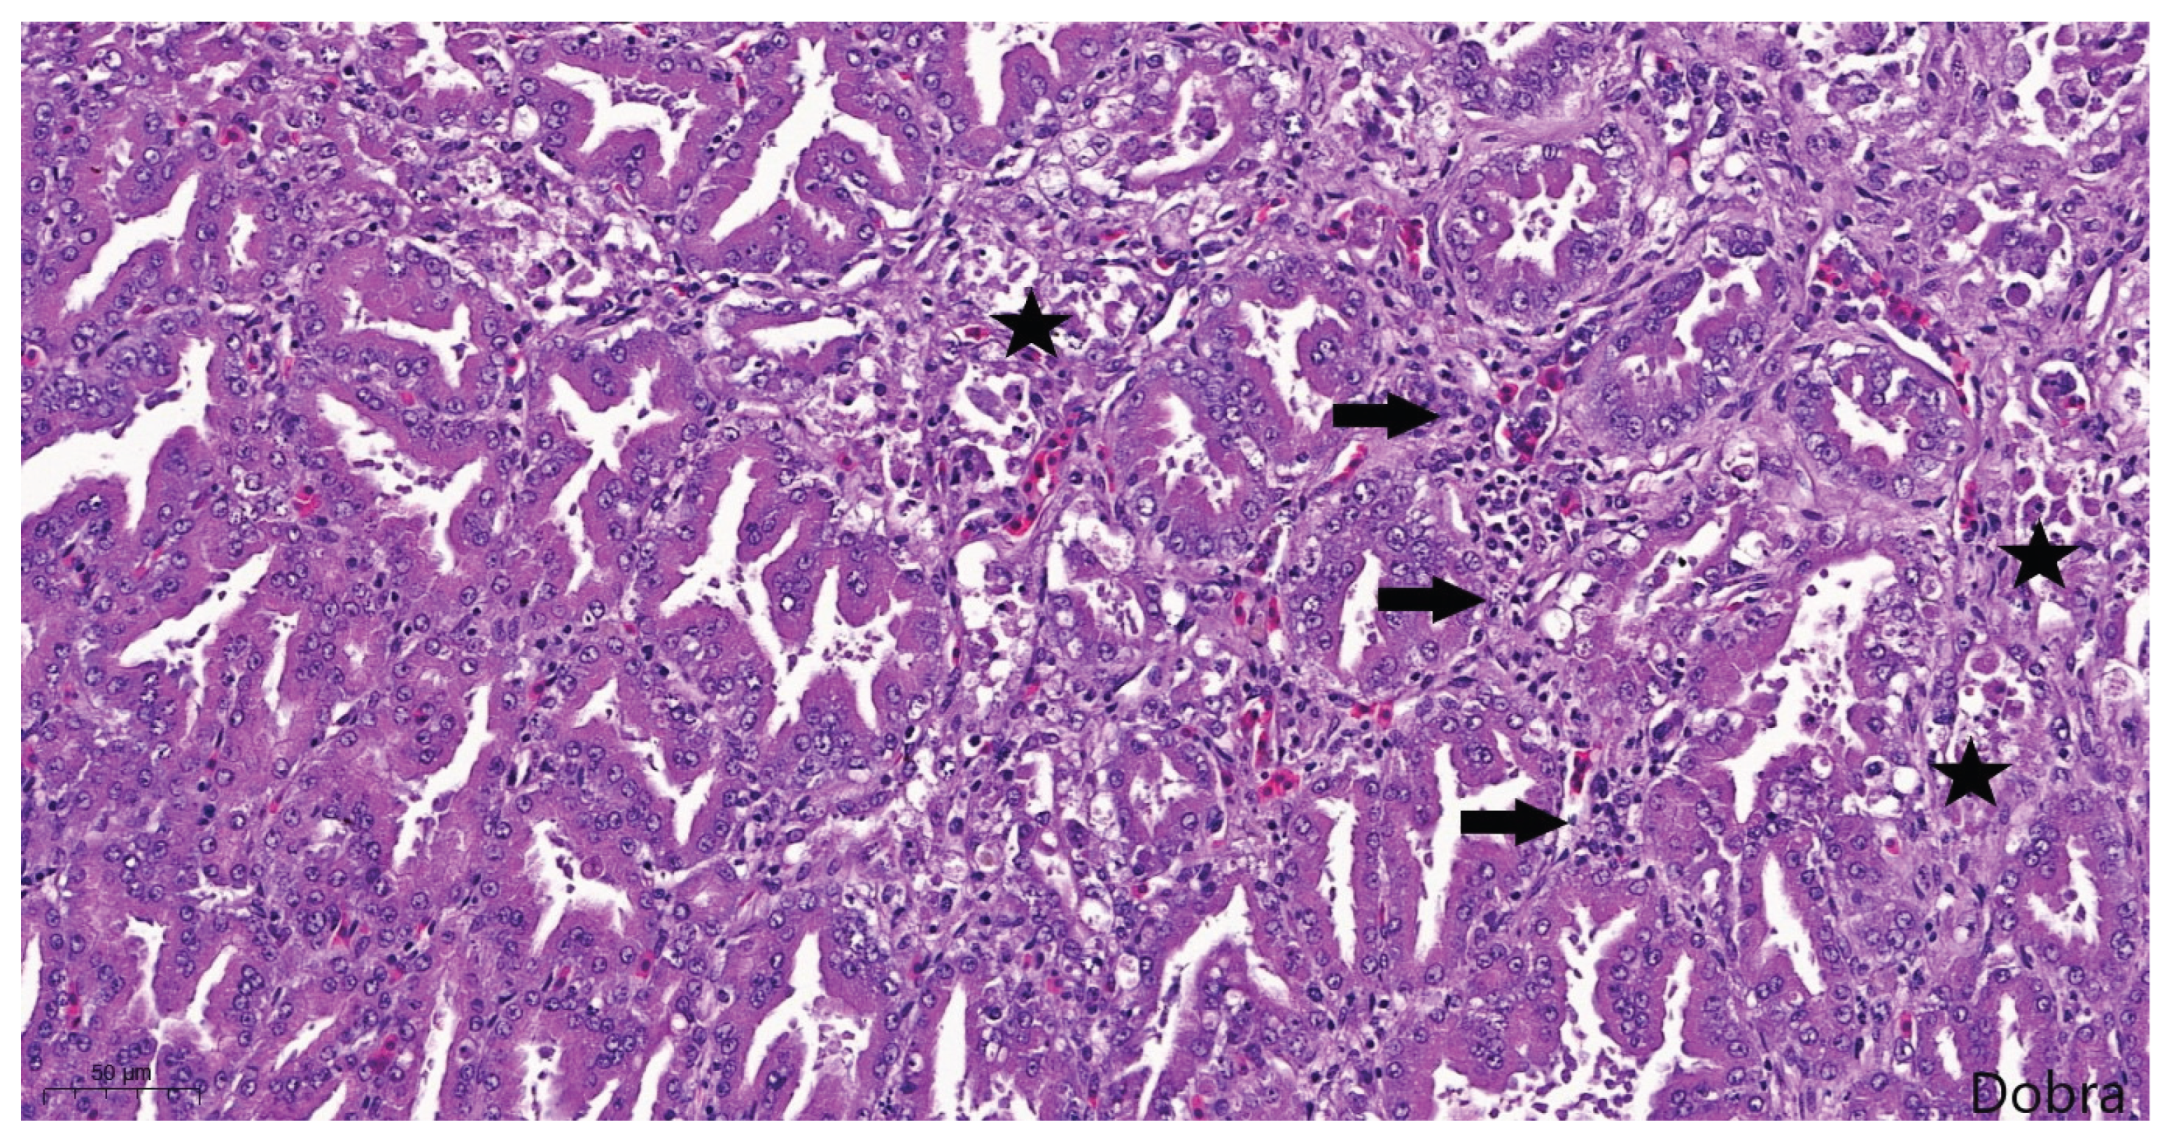

Most proventricular glands exhibited lesions consistent with chronic TVP, including ductal epithelial hyperplasia, epithelial metaplasia, and mild multifocal, lymphocytic infiltration (Figure 10). Masson's trichrome staining confirmed interstitial fibrosis (Figure 11). In addition, acute lesions characterized by glandular epithelial degeneration and necrosis with diffuse lymphocytic infiltration were present in some areas (Figure 12).

Figure 12. Meat-type PS chicken, proventriculus: degeneration, necrosis and detachment of glandular epithelial cells (stars), and mild, diffuse, lymphocytic infiltration of the interstitium (arrows), Haematoxylin-Eosin staining, scale bar = 50 µm.

Histopathological evaluation of proventricular tissues further supported a diagnosis of TVP [2,3,4,5,6,7,8,9,11]. The lesions observed in this study, including glandular epithelial degeneration and necrosis, mononuclear infiltration, epithelial hyperplasia, metaplasia, and varying degrees of interstitial fibrosis, align closely with the classical microscopic features described in experimental infections with TVP-affected proventricular homogenates [2,4,10,28] and CPNV [29]. The concurrent presence of both acute and chronic lesions suggests that the infection in the flock may have persisted or occurred in multiple waves.